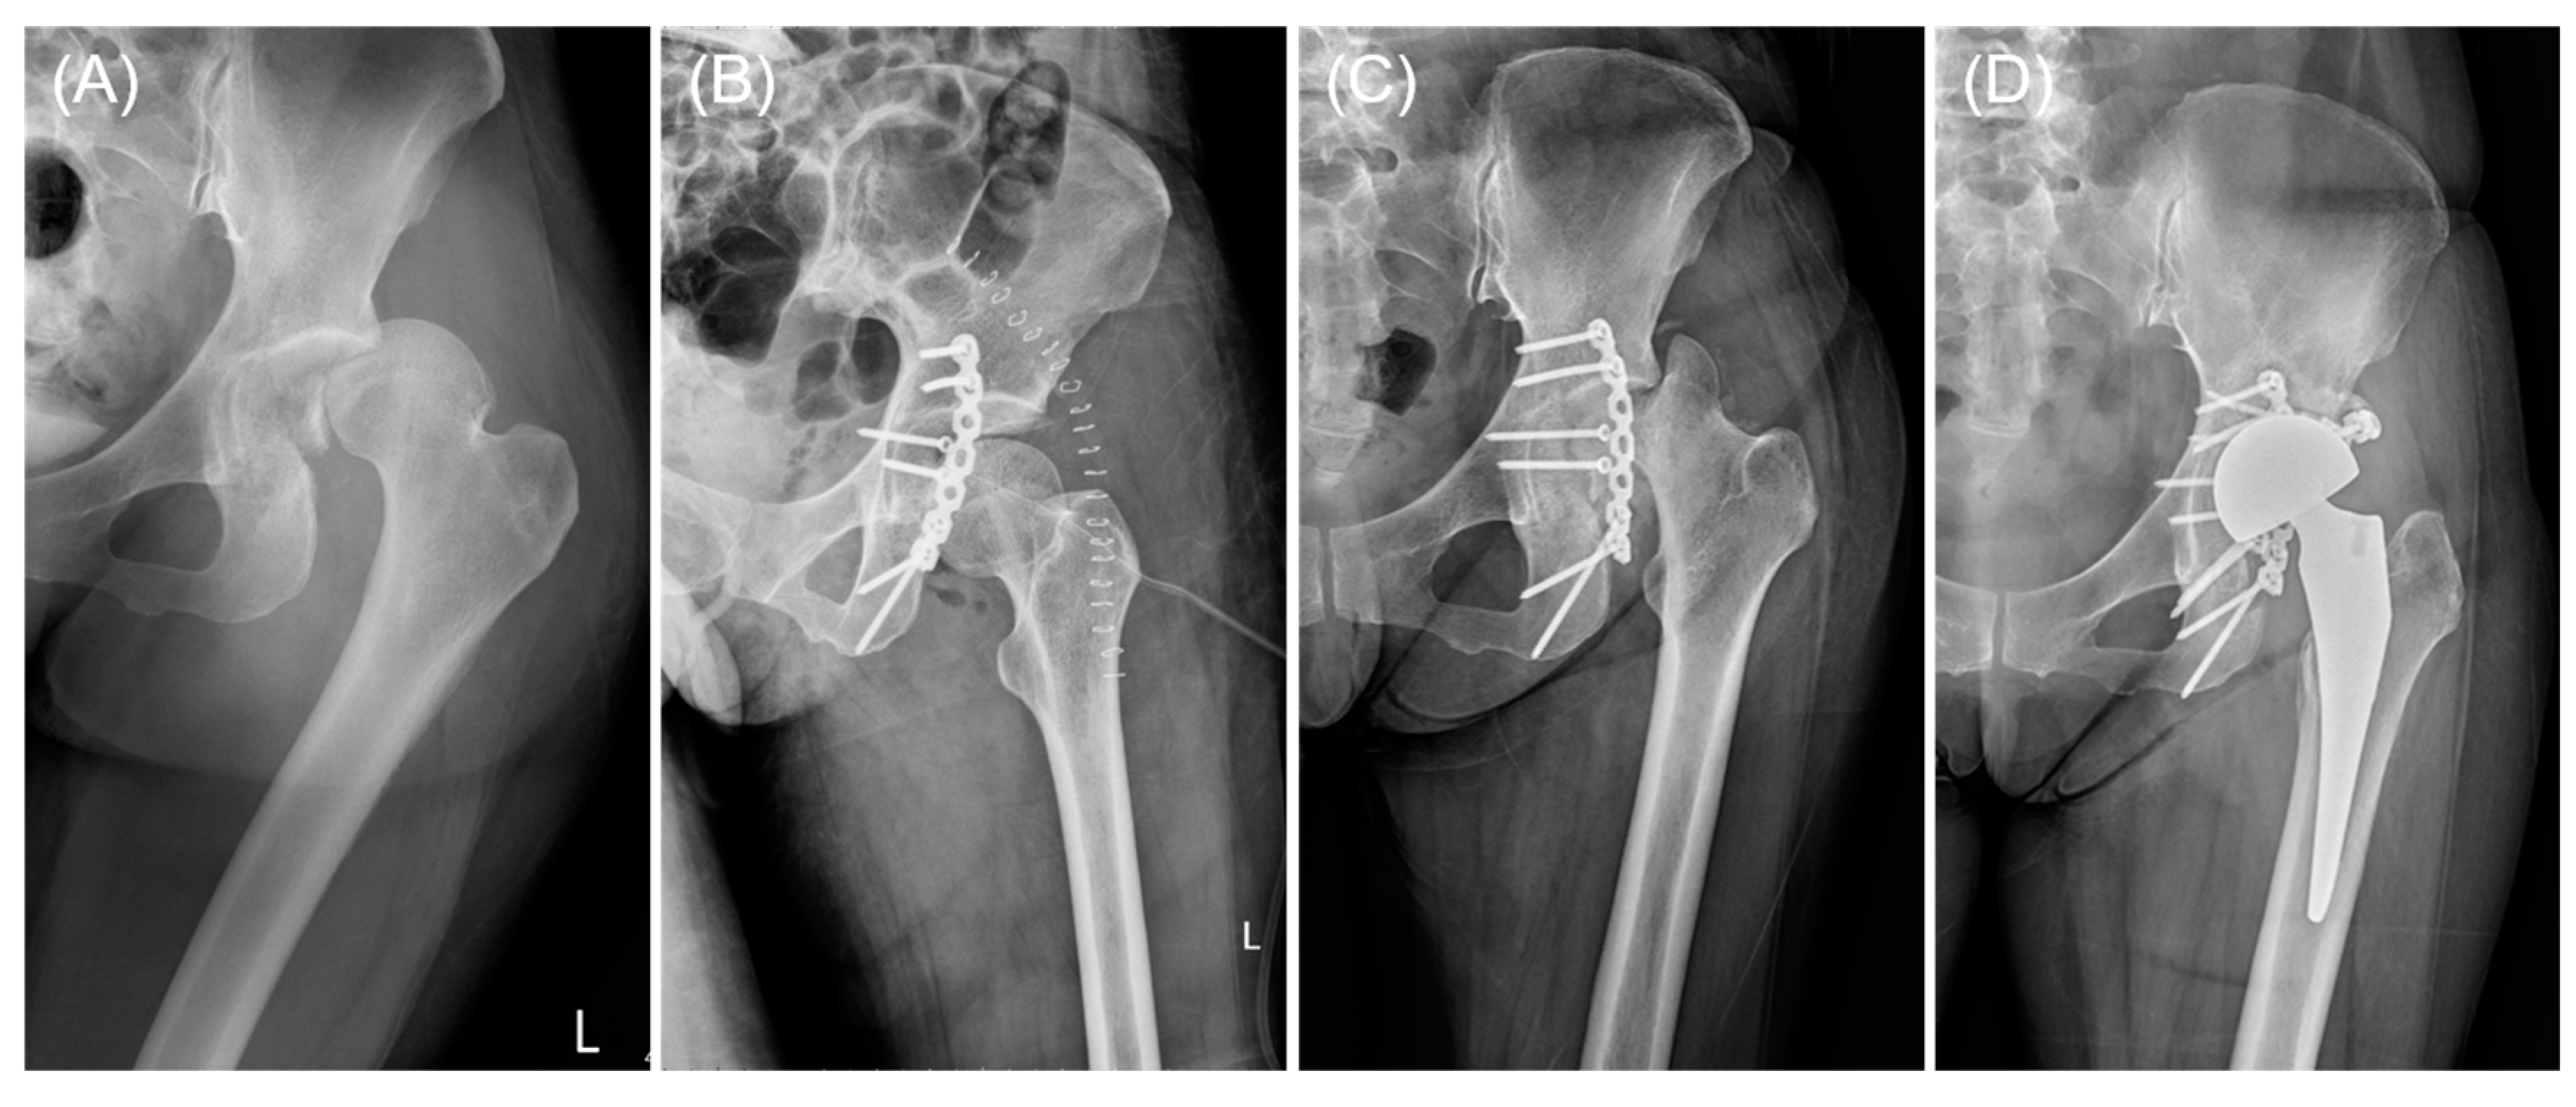

2.3. Implant Design

2.4. Surgical Procedure

3.2. Functional and Radiological Outcomes